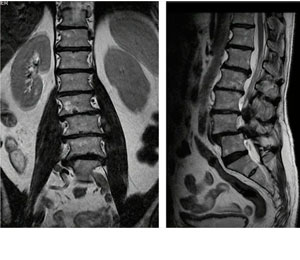

Cifosis rígida toracolumbar (Enfermedad de Scheuermann): varón de 20 años, consulta por dolor toraco lumbar intenso, realizo 4 anos de terapia física y rehabilitación sin éxito. 10 meses Post-operado, se tuvo que realizar varias osteotomías de columna, actualmente sin dolor, realiza actividades cotidianas sin limitaciones.